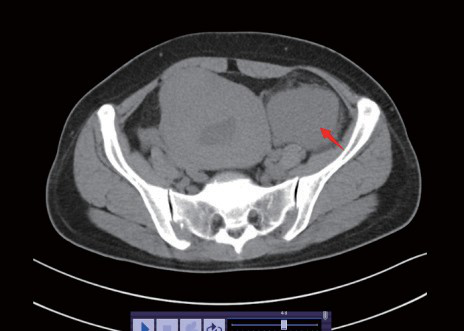

妇科超声:子宫大小 105×107×75mm,边界欠清,子宫壁见多个大小不等实性占位:考虑多发子宫肌瘤。左附件区一 64×45×93mm 实性团块,内见丰富血流信号:颗粒细胞瘤?下腹部 CT(如图 1-3):左附件区见团片状软组织密度影,边界清楚,大小约 5.7×6.6×10.7cm,周围脂肪间隙模糊,邻近腹膜稍增厚,见散在稍大淋巴结影(如图 1-3)。E2、肿瘤标志物(CA199、CA125、HE4)、胸部 CT、上中腹部 CT 等常规检查均无异常。 图 2

CT 表现 :病灶轮廓清楚,密度均匀。